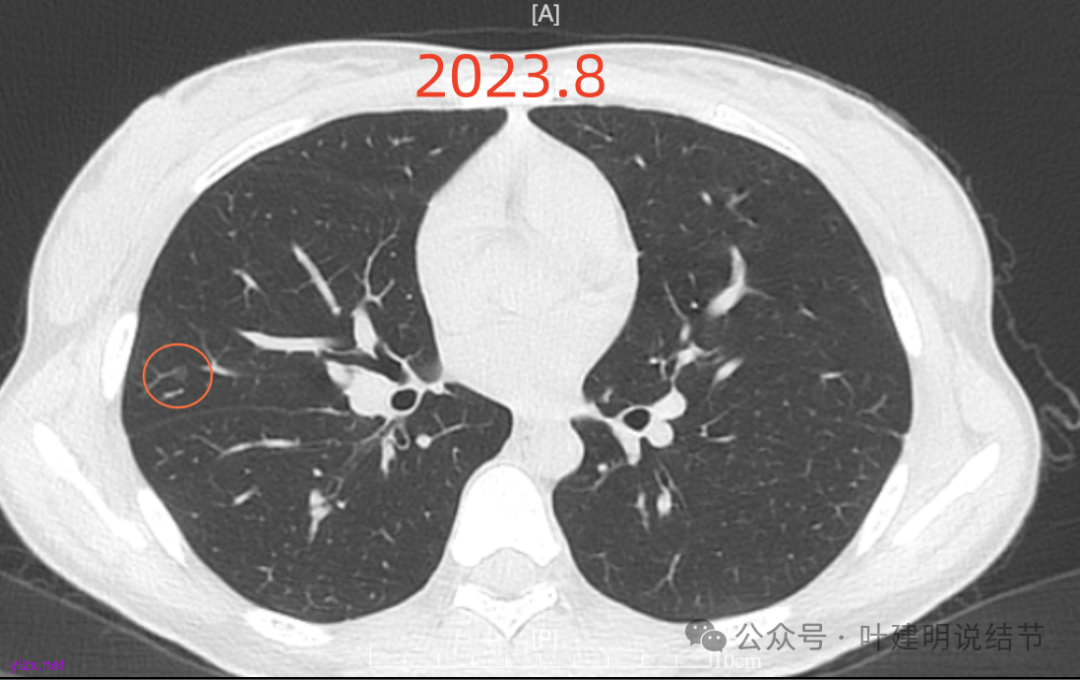

先来看2023年8月的:

病灶6:右下叶脊柱旁囊腔型病灶,整体轮廓与边界清,没有明显实性成分,考虑原位癌或微浸润性腺癌可能性大。